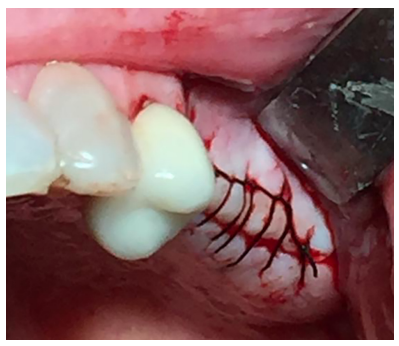

Se realizó una incisión lineal crestal con descarga distal para la obtención del campo quirúrgico. Se utilizó la técnica de fresado biológico a 100 rpm insertándose 3 implantes en posición 25, 26, 27 de 3,5 mm x 10mm (SIN Unitite®), con un torque de 50 N/cm obteniéndose una correcta estabilidad primaria (Figura 11). Tras la colocación de los tornillos de cierre, se procedió a la sutura del colgajo con Supramid® 4/0 aguja 3/8 (Figura 12).